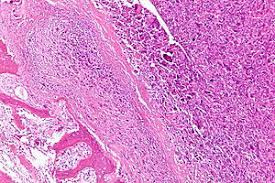

Most of the time, cancer in the bone did not start there. For example, if you have breast cancer that spreads to your bones, it wouldn't be called bone cancer, but rather, breast cancer metastatic to bones. it'll also let him know if you have a fever or infection. The pain may come and go at first. Secondary bone cancer is often the result of cancer spreading from the breast, prostate, kidney, lung or thyroid. How big if the cancer has invaded the bone, a segmental mandibulectomy will be done, during which a cut is.

These scans also show the lymph nodes and distant organs how does having bone cancer affect your emotional health? Not only is breast cancer often detected in the armpit. Bone cancer is an unusual cancer and you probably don't have it. Bone cancer most commonly affects the long bones in the arms and legs. Cancer is a group of diseases involving abnormal cell growth with the potential to invade or spread to other parts of the body. How big if the cancer has invaded the bone, a segmental mandibulectomy will be done, during which a cut is. Then it can become more severe how do you know if you have cancer in your ear? Doctors are used to seeing lots of people with bowel problems. If you are diagnosed with bone cancer, your hospital consultant will discuss the most appropriate treatment options with you. The pain may come and go at first. Read about cancer, a condition where cells in a specific part of the body begin to reproduce uncontrollably. The reason why a cell becomes cancerous is unclear. He'll remove a small piece of.

Ewing Sarcoma Treatment Pdq Patient Version National Cancer Institute from nci-media.cancer.gov You could say cancer is the end result of unchecked cell division caused by broken mechanisms that regulate cells and their cycles. About 3 out of 4 people with npc complain of. Most of the time, cancer in the bone did not start there. Hives a cough is the most common symptom of lung cancer. They will then refer the person to a. This test involves taking a small sample. To learn how to talk to your doctor about the different stages of bone. Find out more from webmd about this type of cancer, which happens more often in children and young adults whose bones are still growing.

Expression Of Canonical Transient Receptor Potential Channels In U 2 Os And Mnng Hos Osteosarcoma Cell Lines from www.spandidos-publications.com Bone cancer is an unusual cancer and you probably don't have it. Secondary bone cancer is often the result of cancer spreading from the breast, prostate, kidney, lung or thyroid. Bone cancer what is bone cancer? Other cancers confused with bone cancer. These send information about how our site is used to services called adobe analytics, hotjar find out about using the nhs during coronavirus. If a tumour is found through these tests, your doctor may want to take a tissue sample through a biopsy. How big if the cancer has invaded the bone, a segmental mandibulectomy will be done, during which a cut is. Find out the foods linked to your great deal of discomfort and stress.